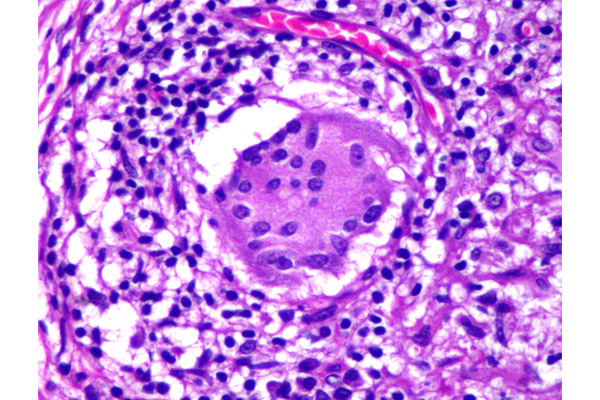

El granuloma está ocupado en casi su totalidad por una gran acumulación de grasa, que se observa como un espacio ópticamente vacío.

En algunas oportunidades, la grasa no se observa fácilmente. Sin embargo, en este campo se reconocen células gigantes de tipo cuerpo extraño, caracterizadas por la distribución al azar de sus núcleos.

En el citoplasma de las células gigantes, y libre en el tejido se puede observar acumulación de lípidos.

Algunas células gigantes pueden contener gotas de grasa y otras estar desprovistas de esta.

Las células gigantes de tipo Touton se pueden observar en esta patología.